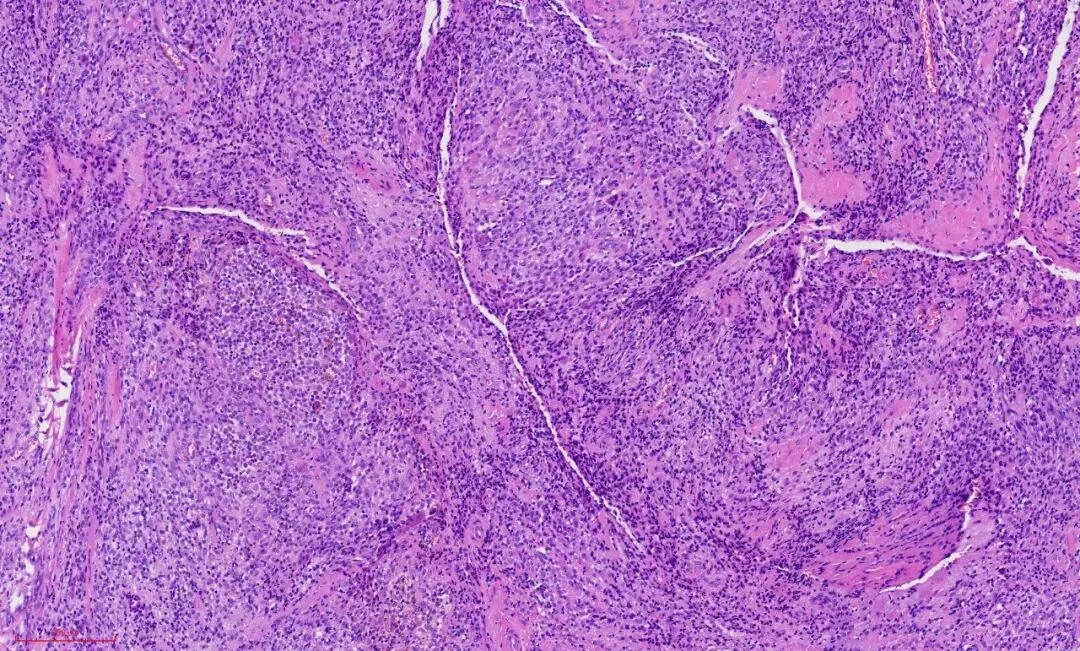

这是一例腱鞘巨细胞瘤。部位:手指。大体:边界清楚,分叶状,切面灰白灰黄。低倍镜下观察肿物边界清楚,如下图:

①肿瘤常有纤维性包膜,界限清楚分叶状或多结节状,可有纤维性间隔。

②常可见破骨样巨细胞(散布于单核细胞之间),含有泡沫样组织细胞反应,炎细胞,可伴有胆固醇裂隙等,间质可胶原化。